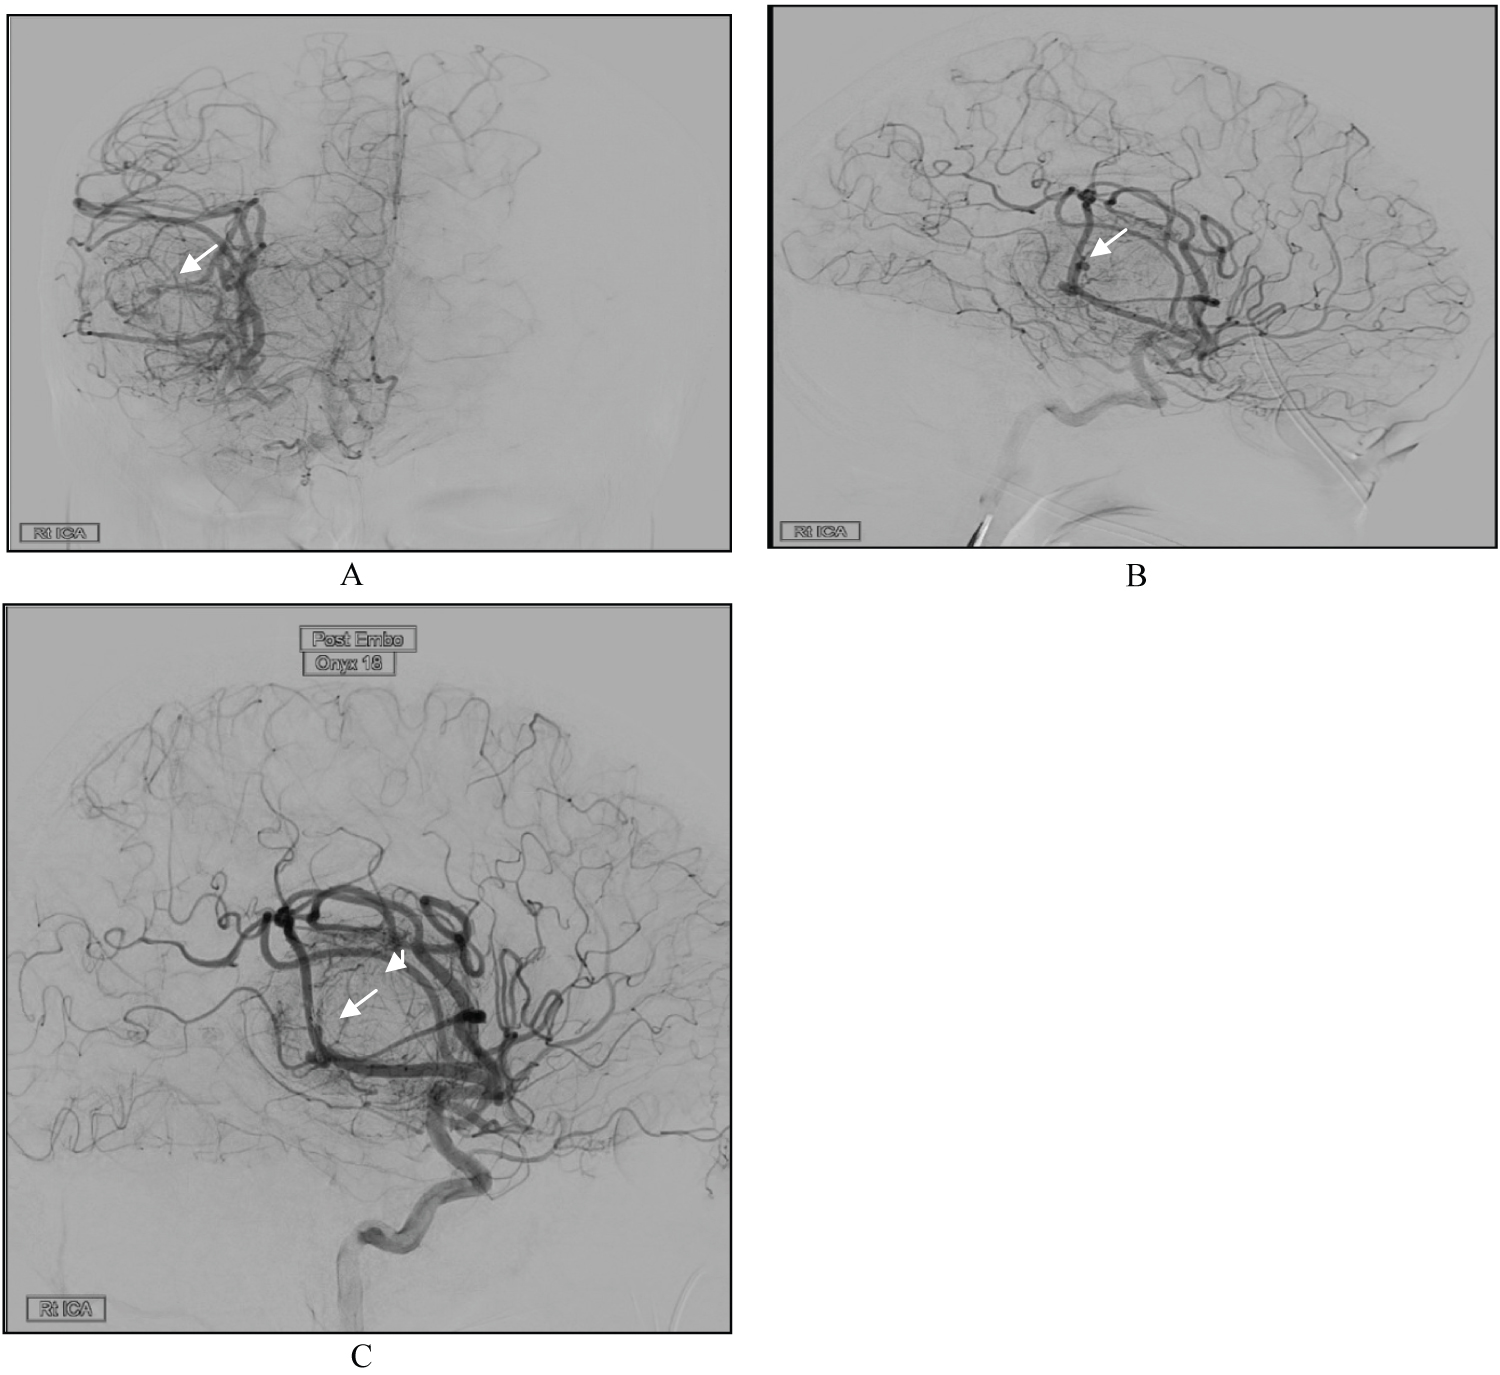

Postoperatively, the patient was kept in the neurocritical care unit (NCCU), where she was sedated and intubated as elected by the anesthesia team due to the long operating time. The next morning, she was still intubated, off sedation and maintaining a Glasgow Coma Scale of 11/15 with reactive pupils, and she could move all limbs freely. On postoperative day 2, she was shifted to the floor with a GCS of 15/15 and no motor or sensory deficits. MRI was obtained (Figure 3); there was debulking of the large lesion in the right frontotemporal area, and residual tumor tissue was seen along the margins of the cavity. There were no territorial ischemic changes. Prior to discharge, cerebral angiography was performed to evaluate the patency of the vessels and to exclude any major radiographic stenosis (Figure 4).

Figure 3: Postoperative MRI showing significant debulking of the tumor with small residual (Arrows) and expected postoperative changes. There were no territorial ischemic changes. (A) Axial view of contrast-enhanced T1WI; (B) Coronal view of contrast-enhanced T1WI. View Figure 3